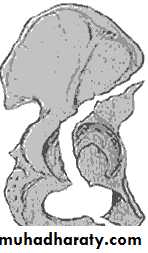

Inter-trochanteric fractures (extracapsular fracture)

.It is extra capsular fracture occurs in elderly..Unite quite easily and seldom cause a vascular necrosis.

The crack runs up between the lesser and greater trochanter.

Pathological anatomy divided into:

Stable:Unstable are those where

a. posteriomedial cortex is shattered.b. poor contact between fracture segment.

The leg is shorter and more externally rotated than intracapsular fracture.